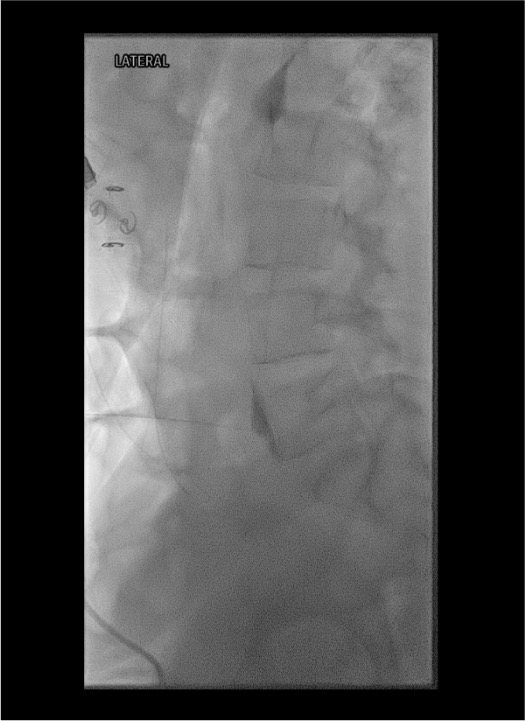

- Needle approach: single midline needle through the sacrococcygeal ligament/junction, just anterior to the sacrococcygeal disc — on lateral fluoroscopy, tip just beyond the ventral cortex of the bone

- Correct contrast pattern: comma-shaped spread in the presacral retroperitoneum on lateral projection

- Indication: perianal and perineal burning pain, sitting-induced pain, coccydynia, anorectal cancer pain — distinct from visceral pelvic organ pain treated by SHP block

- Injection: 3–5 mL 0.5% bupivacaine + 1 mL dexamethasone 4 mg for diagnostic/therapeutic; absolute ethanol 3–5 mL for neurolysis